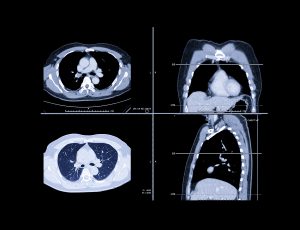

A Chest CT scan is a vital imaging test that creates highly detailed pictures of your lungs, heart, blood vessels, and other structures inside your chest. At Chest Scan Australia, we specialise in Low Dose Chest CT scans to deliver clear results while keeping your radiation exposure as low as possible.